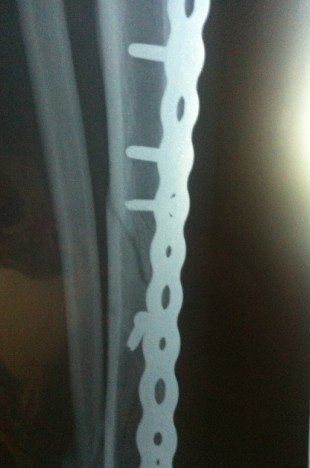

小腿胫腓骨骨折五个月啦,为什么骨折线还那么清晰,跟三个月的拍的片子差不多,这个是骨不连吗?

小腿胫腓骨骨折五个月啦,为什么骨折线还那么清晰,跟三个月的拍的片子差不多,这个是骨不连吗?不用做二次手术吧。现在我应该多下地用双拐走吗?谢谢大家啦

从片子上看,手术应该是成功的,最好能看到整体,那样就更好判抹做断一点,每个人长骨头的快慢不一样,而且即使手术成功,因为其他各种原因,骨头仍谈有不长的,现在还不是特别明确,你可能是个特例呢,是长的慢一点的那种,而且即使骨头长在一起了,骨折线很长时间还是会看到的,我的建议还是再观察几个月,尽量不要剧烈活动,还有要听给你做手术的医生的建议 ,我想现在的医生也怕你们闹的,他们的建议不凡梨碗一定是坏的,一味的责怪医生、医院那些是最不理智的做法,只会给你带来不便,给医生带来影响,恶心循环且解决不了问题。 再谈一点题外话,不要在就医过程中出现问题,就一定是医生的错,真的是医生错了,他逃避责任也逃避不了,行肆如果是正常的意外(包括一些并发症:术后感染、骨折不愈合,骨折愈合缓慢等等,都是正常存在的,几率虽小,在你身上发生就是100% ),请大家多一份理解, 要积极配合医生把并发症产生的后果讲到最低。